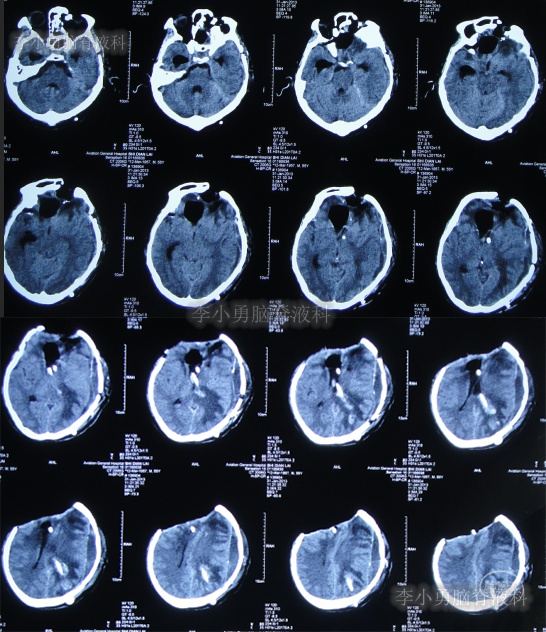

2012年11月1日(开颅术后126天即脑室腹腔分流术16天),转住入李小勇脑脊液科入院时:神志模糊,表情淡漠,肢体不能遵嘱活动,时常有癫痫发作;右额颞顶颅骨缺损,缺损相应区域局部凹陷,自右侧鼻唇沟至头顶有一疤痕,右侧额面部颅骨凹陷(图-6)。头颅CT:脑室腹腔分流术后改变,脑室扩张(图-7)。

图-7:入院时头颅CT

2012年11月5日(入院后5天),进行了原脑室腹腔分流管去除术(右)+侧脑室外引流术(右)。

术后次日查头颅CT示脑室外引流术后(图-8);血培养(厌氧菌):溶血葡萄球菌感染。

图-8:2012年11月6日头颅CT

2012年11月23日(入院治疗23天),引流出血红色脑脊液(图-9);查头颅CT示脑室有缩小(图-10)。

图-10:2012年11月23日头颅CT

2013年1月14日(入院治疗75天),进行了左侧脑室腹腔分流术(图-11);

图-11:2013年1月14日术后头颅CT